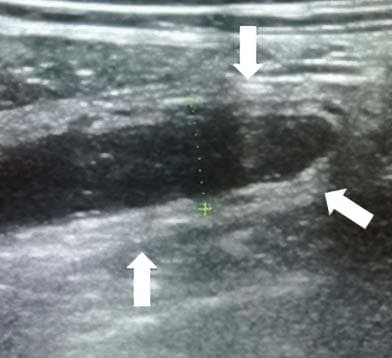

Из протокола УЗИ: «В правой подвздошной области визуализируется слепо заканчивающийся, не перистальтирующий участок кишки 7 мм в диаметре,

наполненный жидкостью, болезненный при компрессии датчиком» (см. рис. 7).

Рисунок 7. Картина УЗИ при флегмонозном аппендиците.